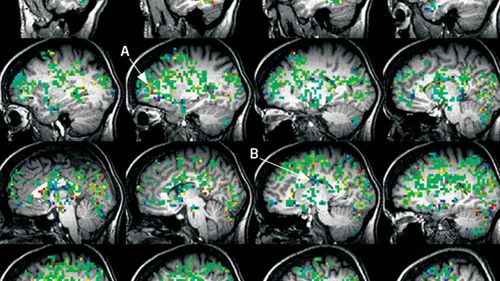

Orgazm otwiera nowe stany świadomości? Tak twierdzą naukowcy 1Kobiecy orgazm krok po kroku - literą A oznaczono korę przedczołową, a B... ośrodek bólu (źródło: NewScientist/Barry Komisaruk)

Zespół Barry'ego Komisaruka z Rutgers University w Newark (New Jersey, USA) wykorzystał skanowanie fMRI, aby zbadać aktywność ludzkiego mózgu podczas szczytowania. Zauważono, że orgazmu nie osiąga się tylko w jeden sposób. Co więcej, niezależnie od metody szczytowania mózg osiąga bardzo nietypowy stan pobudzenia, obejmujący różne ośrodki.

Jednym z nich jest kora przedczołowa, czyli część odpowiedzialna m.in. za... postrzeganie własnej osoby i poprawne relacje społeczne, w tym empatię. Zjawisko to jest najmocniejsze w przypadku kobiet, ale także ludzi płci obojga zdolnych do doprowadzenia się do orgazmu wyłącznie za pomocą wyobraźni. Inne ośrodki ulegające pobudzeniu odpowiadają m.in. za dotyk, pamięć, a nawet ból - aktywuje się również tzw. układ nagrody (w czym nic dziwnego, zważywszy na jego alternatywną nazwę - ośrodek przyjemności).